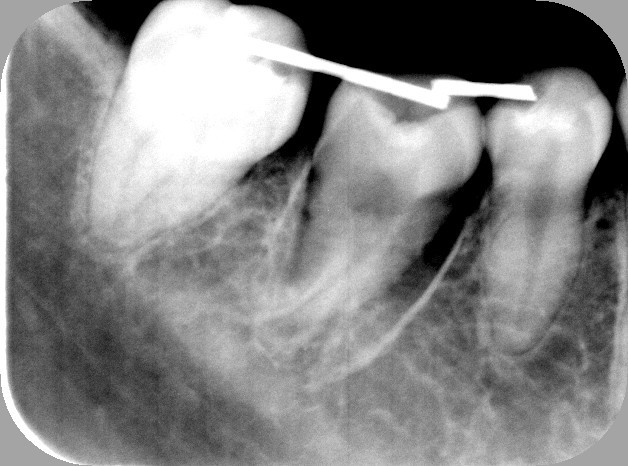

4.移植後3ケ月、骨が出来はじめています。